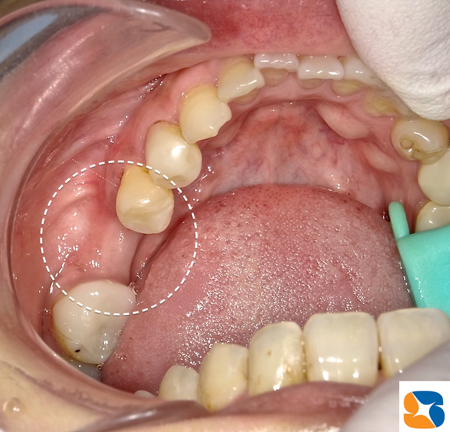

生駒(奈良)より40代の女性が1年前に来院。主訴は「近くで左下の歯を抜いてもらった。途中で麻酔が切れるほど、かなり時間がかかった。入れ歯は嫌だったので、『インプラントは出来ますか?』とその先生に尋ねたら、『骨が薄い(陥没)ので、インプラントは無理です。ブリッジにしますか?』と言われた。ますます骨が無くなっていく事が心配だったので、相談に来た。」でした。確かに、ほっぺた側はインプラントを植立できるだけの骨が失われていた(陥没)ので、骨を増大させるための手術をまず当院で行いました。

その結果、インプラントを植立させることに必要な骨の厚みに仕上がっている事が確認できました。これならインプラントも大丈夫です。